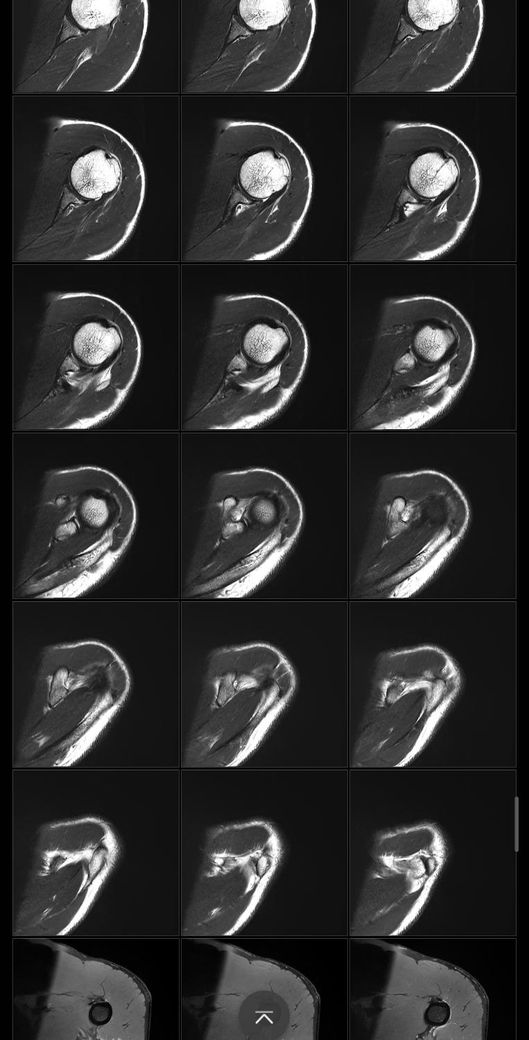

어깨 mri 전문의 소견 부탁드립니다

얼마전에 축구하다가 넘어지고 그날 저녁부터 팔이 안올라가서 건협가서 mri 찍었습니다.

회전근개 파열이 있는지, 없다면 지금 상태가 어떤상태인지와 웨이트 운동 가능할정도의 회복기간이 궁금합니다

Mri에서 별다른 이상소견이 없는 경우 일시적으로 발생하는 움직임이나 기능의 제한일 수 있습니다.

약 2주 이내의 회복기간이 소요될 수 있으며, 현재 mri 사진에서 보이는 염증 소견은 타박상으로 인해서 발생하는 것일 수 있습니다.

별다른 파열의 징후는 보이지 않습니다.

질문하신 내용 잘 읽어보았습니다. MRI결과에서 회전근개 파열 여부가 핵심입니다 부분 파열과 염좌라면 보존적 치료후 6~8주 내 웨이트 복귀 가능하지만 완전파열이면 수술 후 최소 3~6개월 재활이 필요합니다. mri 판독 결과지를 확인해야 정확한 상태와 회복 기간을 판단할 수 있습니다!